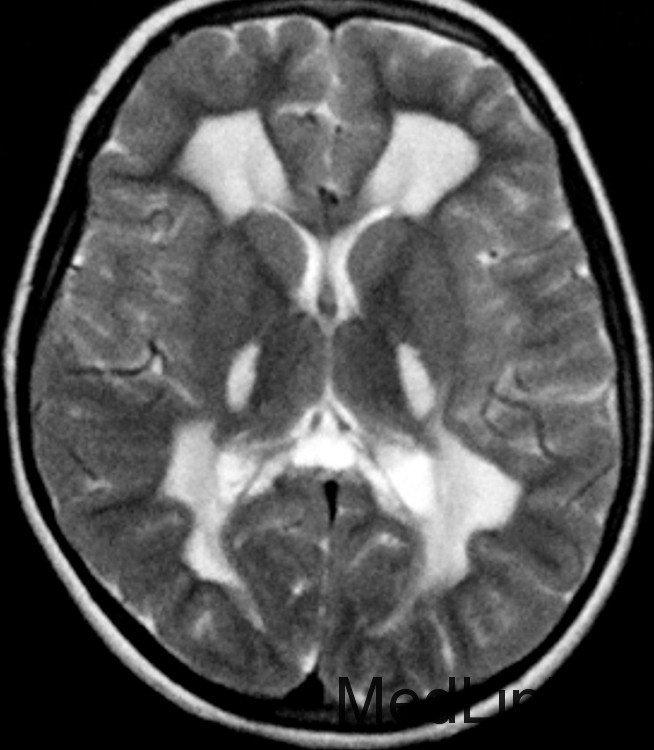

神经科查体显示肌僵直,腱反射亢进,双侧病理征阳性,轻度的小脑共济失调,振动觉及本体觉异常。CSF正常。 T2WI显示幕上及幕下白质T2高信号。内囊后肢、脑干皮质脊髓束、小脑中脚均受累。脊髓T2WI可见皮质脊髓侧束T2高信号。